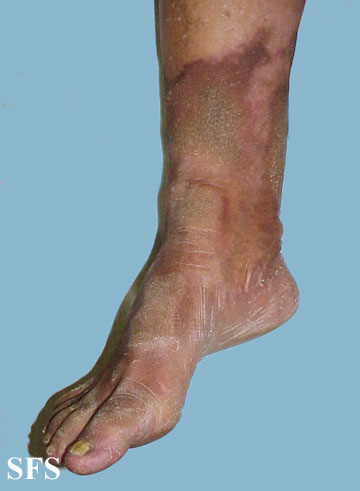

progressive palmoplantar keratoderma